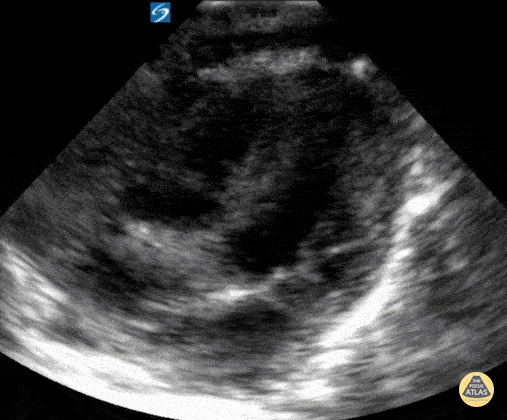

Peds-Cardiac - Normal Neonatal apical 4 chamber view

20 day old neonate presented with shortness of breath. Cardiac POCUS did not reveal any abnormalities. Contributor: Zach Boivin, MD, @ZachBoivinMD